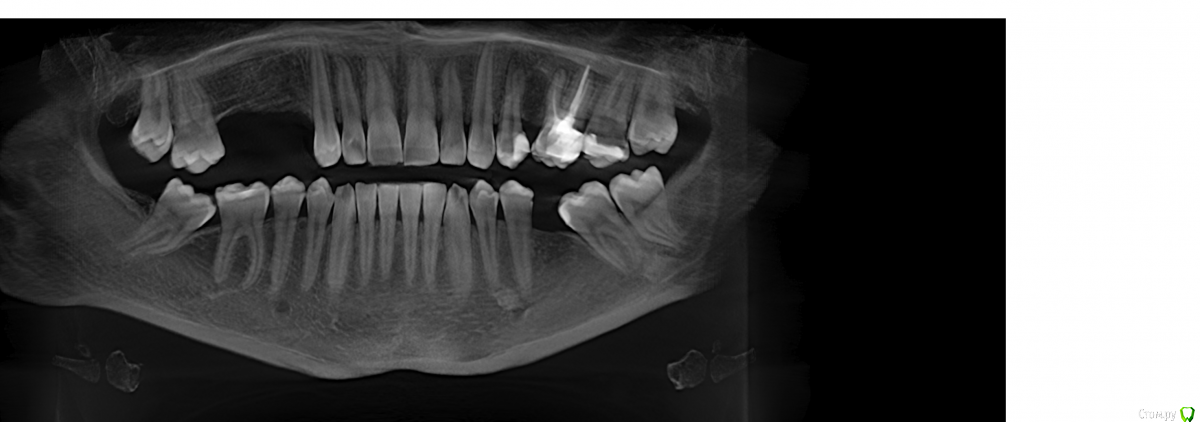

Robinbobin Опубликовано 25 марта, 2015 Поделиться Опубликовано 25 марта, 2015 Имплантаты Dio UF ll,костный материал ауто+остеоматрикс.Хотелось бы услышать мои ошибки 6 Ссылка на комментарий

Robinbobin Опубликовано 25 марта, 2015 Автор Поделиться Опубликовано 25 марта, 2015 я бы обошелся без вертикального разреза, и делал бы разрез по гребню. Почему делали открытый синус? Я делал разрез по гребню но из-за маленького опыта порвал((((Делал открытый потому что объем кости был 2-2.5 мм а боком поставить побоялся) Ссылка на комментарий

red_butler Опубликовано 25 марта, 2015 Поделиться Опубликовано 25 марта, 2015 Делал открытый потому что объем кости был 2-2.5 мм а боком поставить побоялся) все, увидел, конечно открытый Ссылка на комментарий

колесников Опубликовано 25 марта, 2015 Поделиться Опубликовано 25 марта, 2015 Вестибулярная компактная пластинка резорбируется на 3 мм у шеек имплантов. Вы конечно оставили дополнительно остеоматрикс вестибулярно ? В области 14 обязательно подсадите стт, можно на этапе формирователя. 16 можно было и короче взять,тогда бы он целиком находился в материале. А в целом Всё достойно. Ссылка на комментарий

Тимур86 Опубликовано 25 марта, 2015 Поделиться Опубликовано 25 марта, 2015 У пациента часом гайморита нету? Ссылка на комментарий

Robinbobin Опубликовано 26 марта, 2015 Автор Поделиться Опубликовано 26 марта, 2015 У пациента часом гайморита нету?До операции пазуха была забита и я отправил к лорикам они дали мне добро и выдали справку Ссылка на комментарий